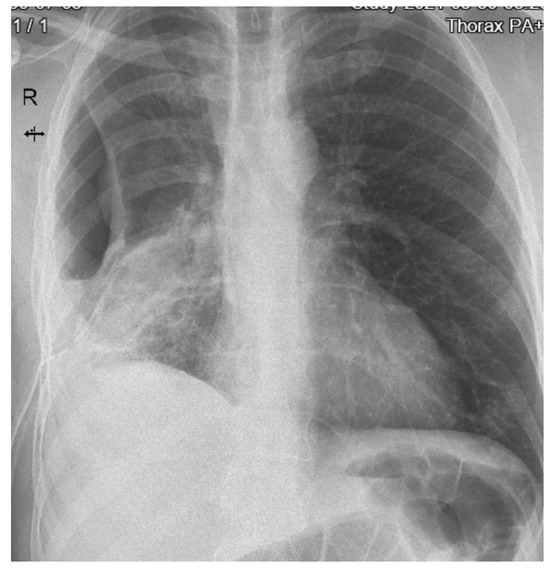

On the fourteenth day, the number of leucocytes and inflammatory markers continued to increase (L = 42.000 cells/mm3, ESR = 30 mm/1 h, C-reactive protein = 102 mg/L) and the chest X-ray found reticulomicronodular opacities with pleural effusion on the right (Figure 2).

Figure 2. Chest X-ray (day 14) showing pleural effusion.